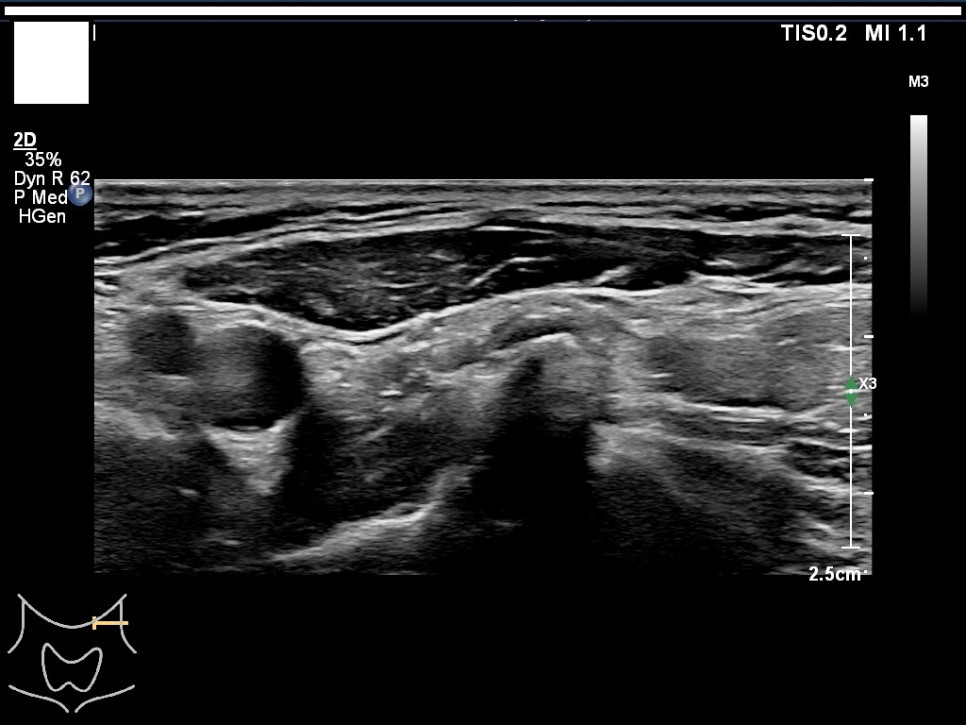

Color Doppler / 우측 경부 림프절 Level1-4 / 우측 경부 림프절 level5

좌우 이하 선 악하선 가로 스캔 1, 2 / 좌경부 림프절 level 1-4

좌경부 림프절 5/우엽 중부 가로 스캔/우엽 중앙부 세로 스캔

우경부림프절/좌엽중앙세로 스캔/좌엽중앙가로스캔

좌측 경부 림프절 / 중심 경부 림프절 / 협부 옆 스캔 2. 판독 소견서가) 등록 번호, 성명, 생년월일 또는 연령, 성별, 검사명, 검사 일시, 판독 일시, 검사와 판독한 의사(면허 번호), 의료기관명, 검사 소견 및 결론 나) 검사 소견에는 갑상선 에코, 병변의 유무를 기술하여야 한다. 결절이 있을 경우 위치, 최대지름, 주요 소견, K-TIRADS의 내용을 기술하여야 하며, 암으로 진단된 결절을 추적할 경우 위치, 3방향 직경, 주요 소견, 전 검사와 변화 여부, 경부 림프절의 평가 및 이상 소견 여부를 기술하여야 하며, 경부 림프절에 이상이 있을 경우 위치, 크기, 주요 소견을 기술하여야 한다. 결절이 여러 개 있을 경우 암 위험도에 따라 선택적으로 기술할 수 있다. 또 소아 등에서의 환자의 협력도 음창 등이 좋지 않아 표준 영상 획득에 제한이 있는 경우 추가 기술해야 한다.